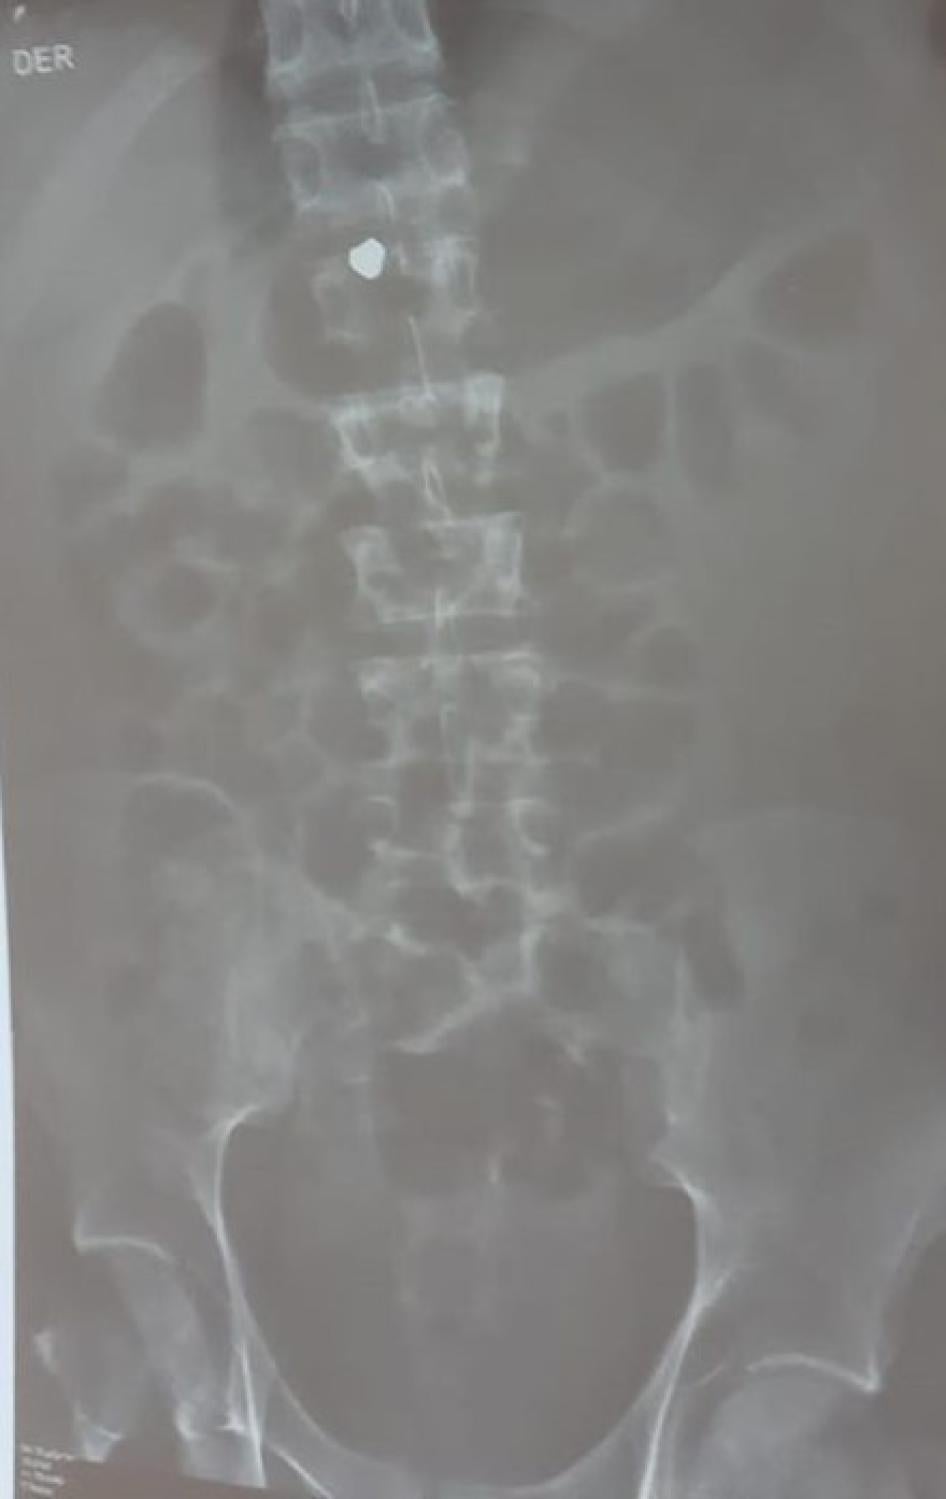

X-ray showing a pellet, believed to be lead, lodged in Jon Cordero’s spinal cord. Photograph courtesy of Jon Cordero’s family.